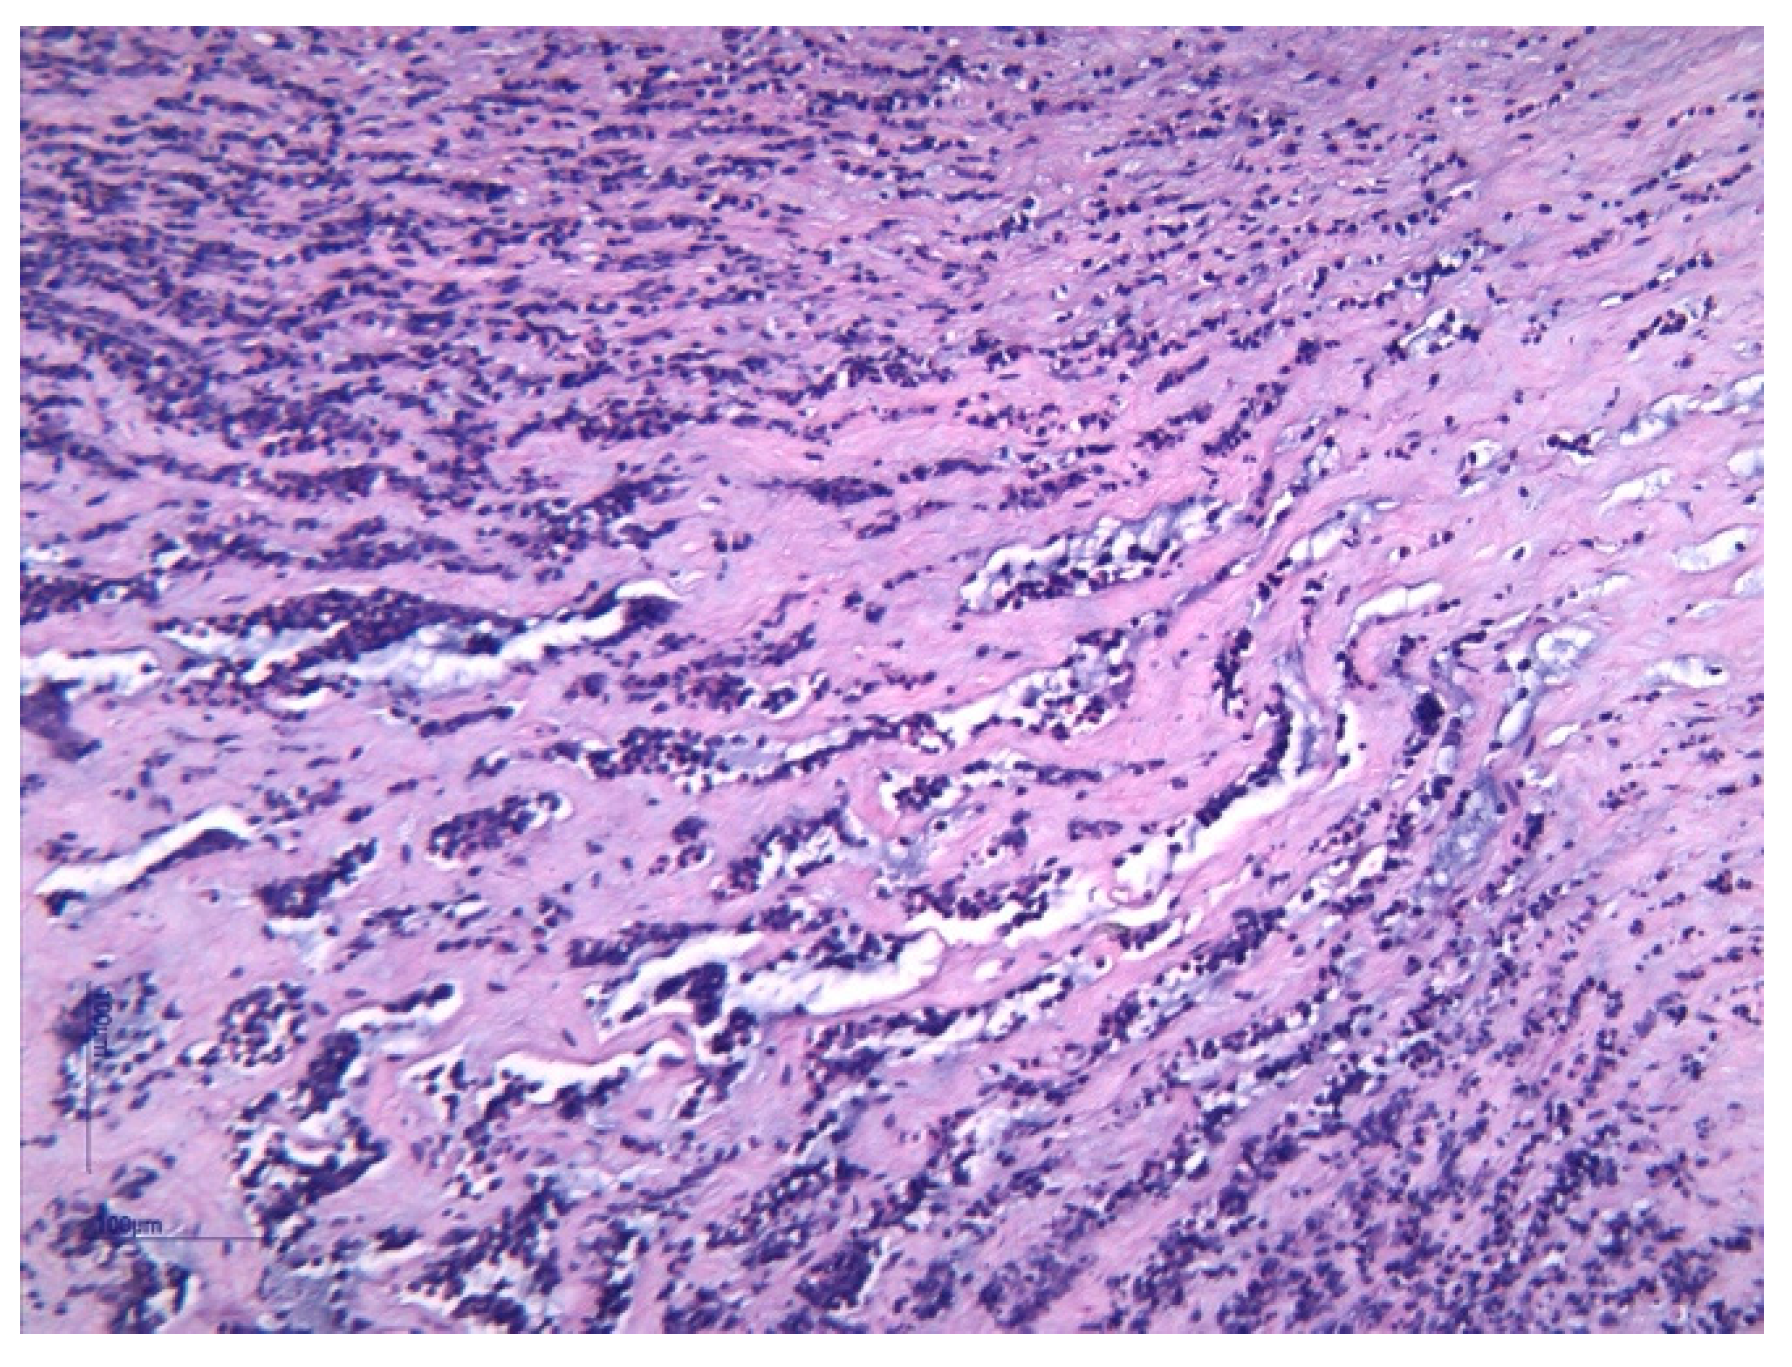

- Pacora, P.; Chaiworapongsa, T.; Maymon, E.; Kim, Y.M.; Gomez, R.; Yoon, B.H.; Ghezzi, F.; Berry, S.M.; Qureshi, F.; Jacques, S.M.; et al. Funisitis and chorionic vasculitis: The histological counterpart of the fetal inflammatory response syndrome. J. Matern. Neonatal Med. 2002, 11, 18–25. [Google Scholar] [CrossRef]

- Kim, C.J.; Romero, R.; Chaemsaithong, P.; Chaiyasit, N.; Yoon, B.H.; Kim, Y.M. Acute chorioamnionitis and funisitis: Definition, pathologic features, and clinical significance. Am. J. Obstet. Gynecol. 2015, 213 (Suppl. 4), S29–S52. [Google Scholar] [CrossRef] [PubMed]

| Corioamnionitis (n = 42) | 37 (88.1%) | 5 (11.9%) | 0.001 | |